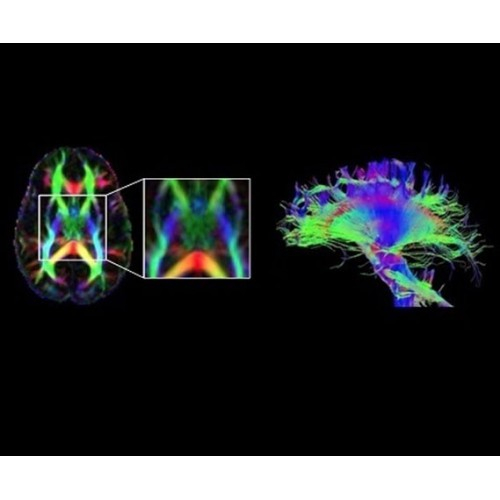

В систему SIGNA PET/MR встроены запатентованные детекторы кремниевого фотоумножителя (SiPM) и сверхчувствительные кристаллические сцинтилляторы на основе лютеция толщиной 25 мм. Благодаря этому обеспечивается исключительная чувствительность и возможность использования времяпролетной диагностики (TOF).

Кроме того, в результате использования технологии TOF и инновационной технологии реконструкции Q.Clear вы сможете добиться прекрасного соотношения сигнал/шум. А благодаря технологии нулевого времени эхо (ZTE) визуализировать костную структуру без ионизирующего излучения. Все эти разработки для улучшения качества сканирования и точности анализа помогут вам использовать весь потенциал ПЭТ/МРТ.

• Q.Clear — в основу технологии легли накопленные знания о том, как минимизировать помехи при реконструкции и получить четкое изображение. При значительном улучшении качества изображения сохраняется точность расчетов. Сочетание технологии TOF и реконструкции Q.Clear — ваш надежный помощник для получения точных и достоверных данных.

• МРТ с функцией нулевого времени эхо (ZTE) отличается точностью, возможностью персональных настроек и отсутствием ионизирующего излучения. Она приходит на смену традиционному исследованию на основе рентгеновского излучения. МРТ с функцией нулевого времени эхо (ZTE) на базе SIGNA ПЭТ/МРТ является более надежной и быстрой по сравнению с системами, использующими сверхмалое время эхо (UTE).